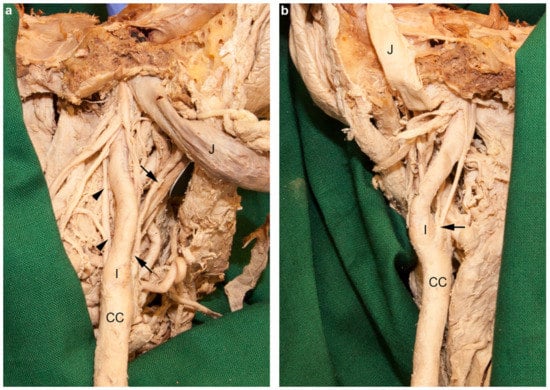

3.4. Aberrant Right Subclavian Artery and Bicarotid Trunk

4.4. Aberrant Right Subclavian Artery and Bicarotid Trunk